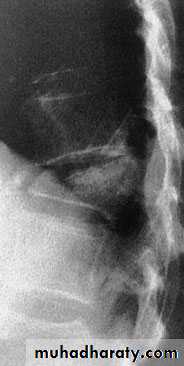

Thoracic Spine X Ray

Lateral radiograph